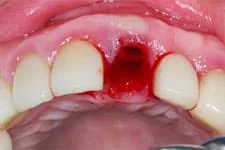

3. 即拔即種

打破傳統即拔即種(又叫立即植牙),拔牙後立刻植牙。患者可在拔牙後立即植入人工植體,並立刻裝戴假牙。讓你治療當天就能擁有美觀的門面。

我們在植牙領域的突破,克服患者對手術的恐懼,也同時幫助患者告別了缺牙的痛苦,讓患者重新擁有一口完美的牙齒。

↑ 治療後:微創立即植牙恢復美麗外觀